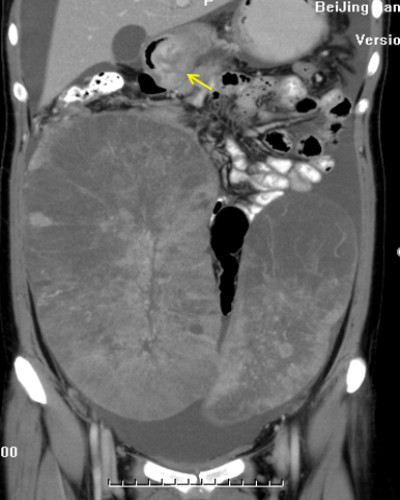

图片(箭头所示为增厚的胃壁,即胃癌原发灶;腹腔中的两个20~30厘米的巨大肿物为卵巢转移灶)

就像这位女性患者,25岁,非常年轻,当时就是觉得肚子有点鼓,也不疼,没有明显的不适症状。她也是先做的B超发现了肿块,后又做了CT,结果一看,腹盆腔里有一个直径30多厘米和一个直径20厘米的大瘤子,仔细观察又发现她的胃壁也有增厚,后来进一步胃镜检查确诊是胃癌。她其实是胃癌转移到了双侧的卵巢,已经是晚期了,但也没有明显症状。原因其实跟肿瘤所处的位置有关。

对于腹盆腔或胸腔而言,由于它们的空间都是比较大的,所以这里面的肿瘤有时就能长得比较大而不引起明显症状。但是有一些比较小的或者是长在比较重要位置的肿瘤,比如说在椎管或脑里边的肿瘤,由于椎管里的空间很狭小,直径不到1厘米的肿瘤就可能明显压迫脊髓或神经根出现症状;脑作为神经中枢,小的肿瘤也很可能影响所在脑区支配的肢体进而出现症状,如小脑肿瘤患者会出现走路不稳等问题。